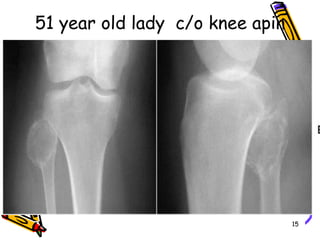

51 year old lady  c/o knee apin15

patients with soft tissue tumors rarely complain of pain but more often complain of a mass. Exceptions to this rule are patients with nerve sheath tumors who have pain or neurological signs. 16